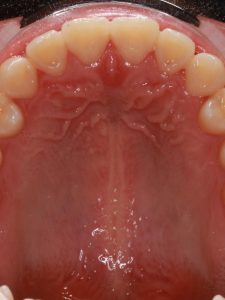

Before and After Images